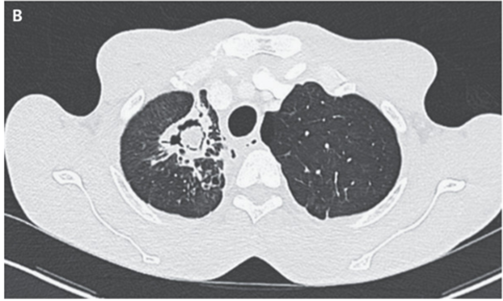

再度CT施行。右上肺の空洞壁の肥厚と新規空洞内腫瘤を認めた。